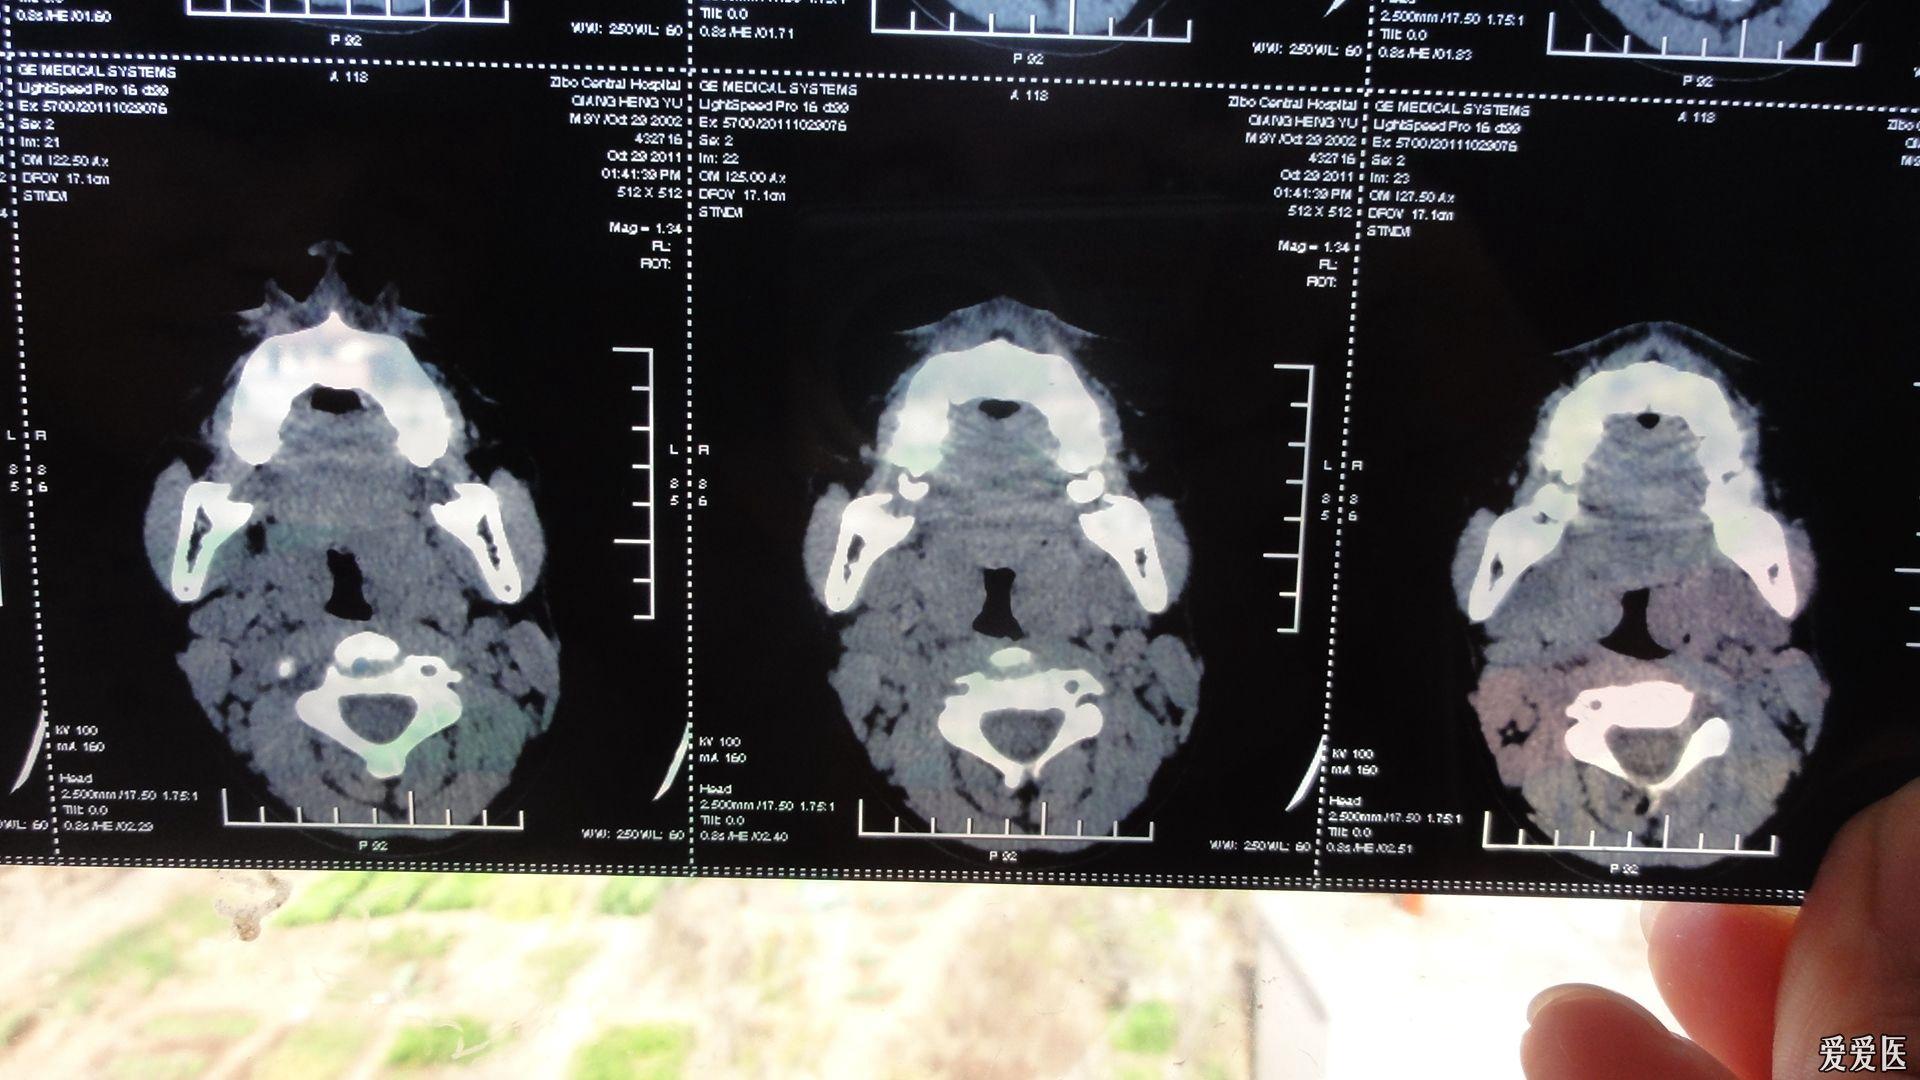

内科大夫求助增殖体肥大